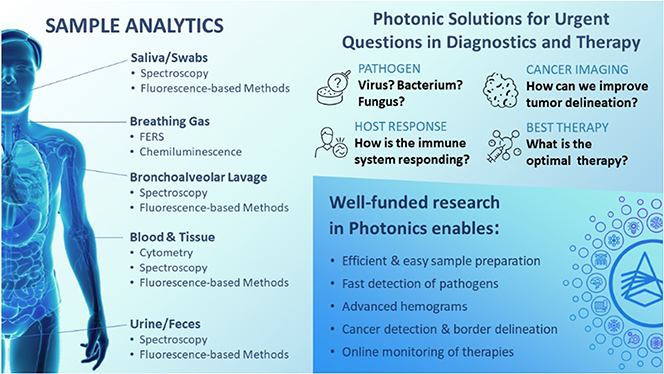

Henry Chapman and Jürgen Popp describe the benefits of light for health. Jürgen Popp is considering the use of lasers that have advanced tremendously in recent years in terms of power stability and wavelength tunability. Modern lasers are used in several crucial roles in cell imaging, disease diagnosis, and precision surgery. Henry Chapman considers the use of free-electron lasers for understanding features and processes in structural biology. He shows that the advance of those electron accelerator-based machines has allowed tremendous progress in the determination of the structures of biomolecules and the understanding of their function.

Aleksandra Walczak, Chiara Poletto, Thierry Mora, and Marta Sales describe physics research against pandemics, a multi-disciplinary problem at the crossing of immunology, evolutionary biology, and networks science. Pandemics are also multi-scale problems at the spatial and temporal levels: from the small pathogen to the large organism; and from the infective process at cellular scale (hours) to its propagation community-wide (months). Simple mathematical models such as SIR (susceptible-infected-recovered) have been a source of inspiration for physicists who model key quantities at an epidemic outbreak, such as the effective reproductive number R, in situations where a disease has already spread. A prominent example is the recent COVID-19 pandemic that has been more than a health and economic crisis. It illustrates our vulnerability where interdisciplinary and multilateral science play a crucial role addressing a global challenge such as this.